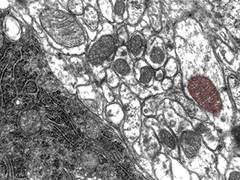

Zellen im Elektronenmikroskop. Ein Mitochondrium einer Zelle wurde nachträglich

Zellen im Elektronenmikroskop. Ein Mitochondrium einer Zelle wurde nachträglich am Rechner rot eingefärbt. Copyright: Hartwig Wolburg / Universität Tübingen